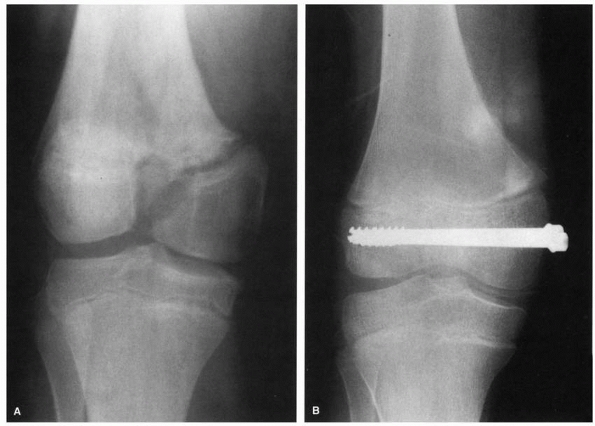

FIGURE 23-9 A.

Salter-Harris type III fracture-separation of the distal femur. Note the vertical fracture line extending from the physis distally into the intercondylar notch with displacement. B. After reduction and fixation with two compression screws extending transversely across the epiphyseal fragments. Note closure and healing of the vertical fracture line in the epiphysis, with restoration of the articular surface. |